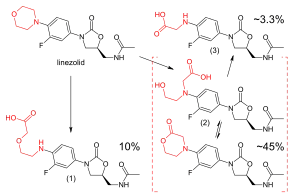

Linezolid is metabolized in the liver, by oxidation of the morpholine ring, without involvement of the cytochrome P450 system. This metabolic pathway leads to two major inactive metabolites (which each account for around 45% and 10% of an excreted dose at steady state), one minor metabolite, and several trace metabolites, none of which accounts for more than 1% of an excreted dose.[104] Clearance of linezolid varies with age and gender; it is fastest in children (which accounts for the shorter half-life), and appears to be 20% lower in women than in men.[4][104][105] There is a strong correlation between linezolid clearance and creatinine clearance.[106]